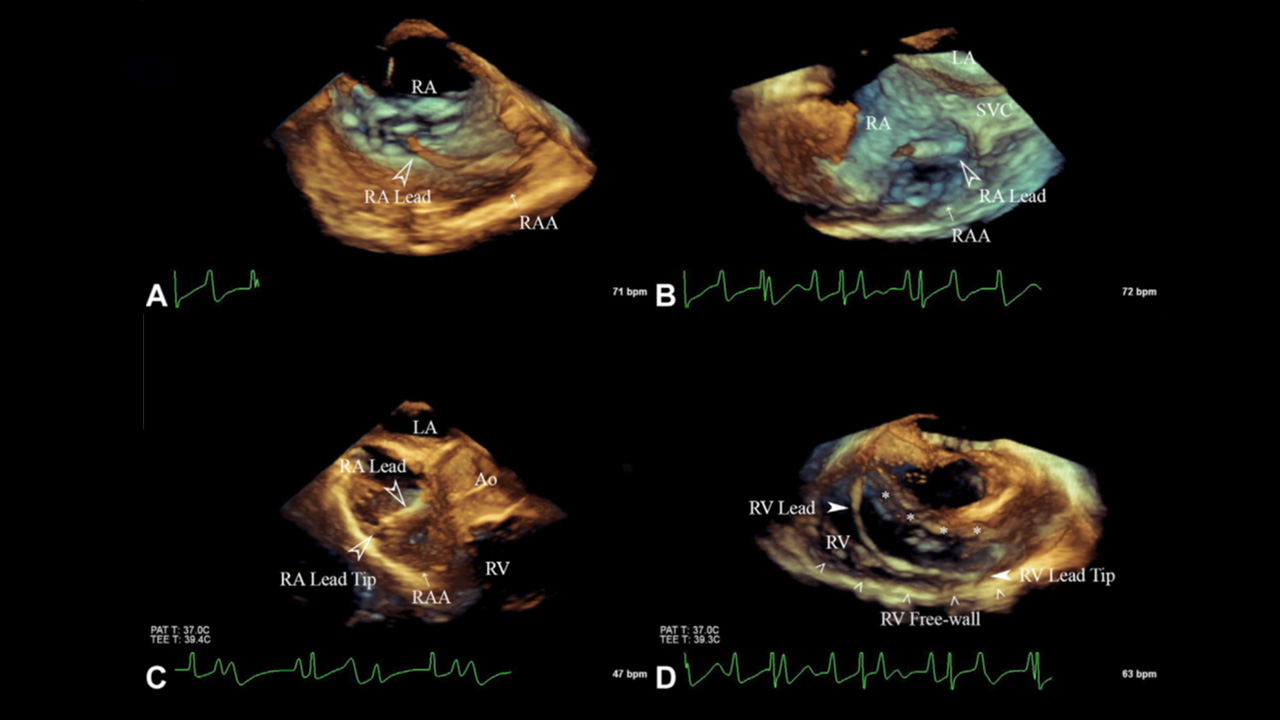

Placing leads in patients with pacemakers and implantable cardioverter-defibrillators (ICDs) traditionally uses fluoroscopy, which is an X-ray based technology. Inherent limitations in this imaging modality can result in leads being placed in suboptimal locations, which may put patients at risk for long-term cardiac dysfunction, all while exposing patients and staff to radiation.

After analyzing 59 cases and 72 controls, our team found that 3DE guidance for pacemaker and ICD lead placement improves the accuracy of lead placement to the desired location over fluoroscopic guidance alone, with significantly decreased radiation exposure and a trend toward improved electrical conduction patterns. The data presented here suggest that the use of 3DE for transvenous lead placement results in multiple short- and long-term benefits to both patients and staff.